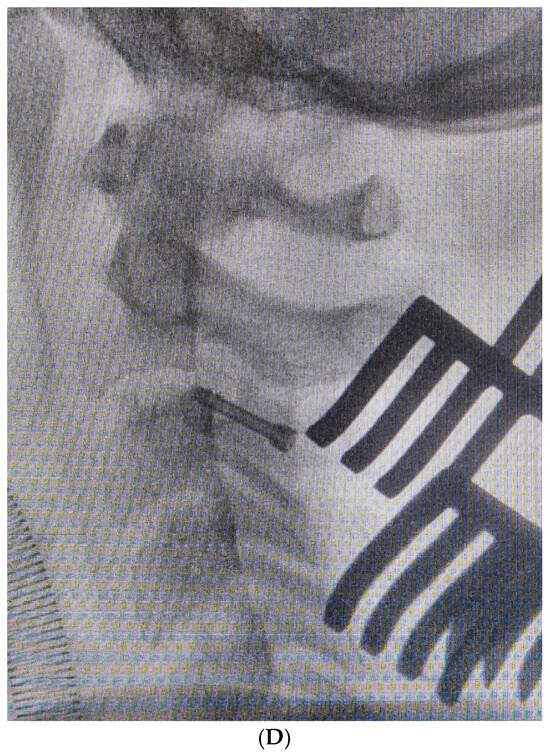

2. Materials and Methods

2.1. Preoperative Planning

2.2. Surgical Technique